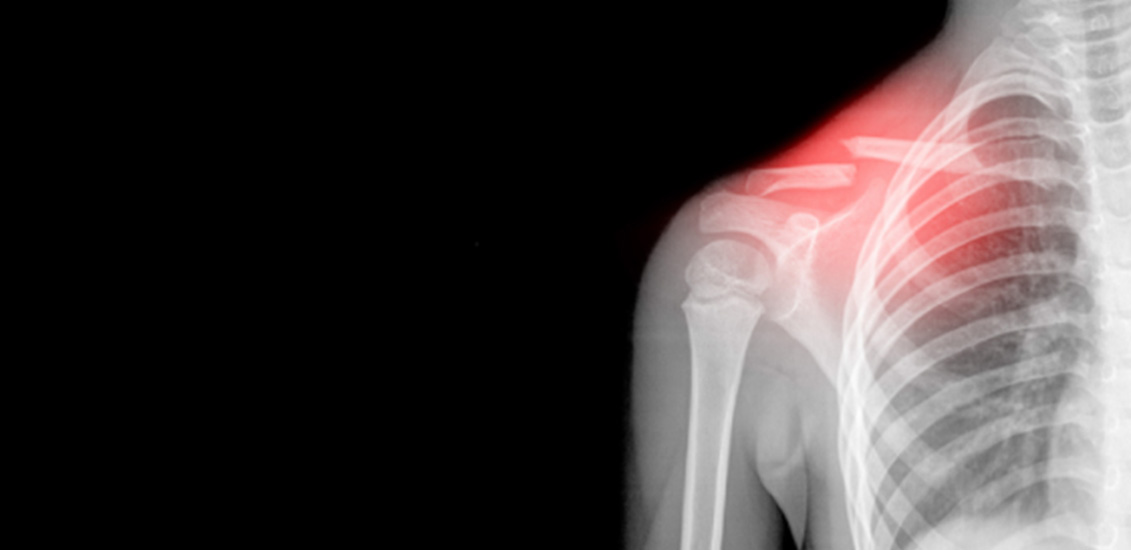

°ÇÑ ¿ÜºÎÀÇ Ãæ°ÝÀ¸·Î ÀÎÇØ »ÀÀÇ ÀϺΰ¡ ¼Õ»óµÇ°Å³ª ºÎ·¯Áø »óŸ¦ ¸»ÇÕ´Ï´Ù. ´ë°³ÀÇ °æ¿ì »À¿¡ °ÇÑ Ãæ°ÝÀÌ °¡ÇØÁ³À» ¶§ ¹ß»ýÇÕ´Ï´Ù. »ÀÀÇ ÁÖº¯ÀÇ ¿¬ºÎ Á¶Á÷µîÀÇ ¼Õ»óÀÌ µ¿¹ÝµÇ´Â °ÍÀÌ ´ëºÎºÐÀÔ´Ï´Ù.